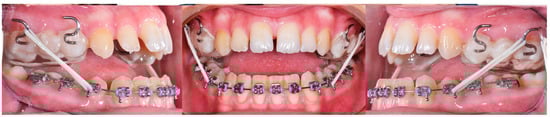

3. The Results of the Treatment